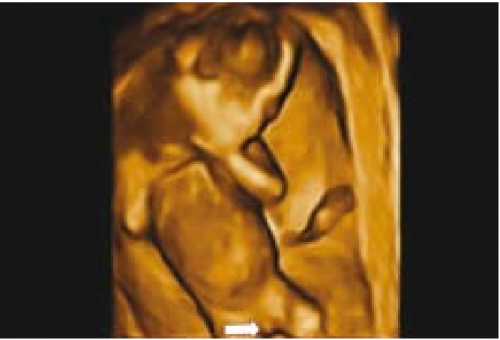

השתנה עוברית - 30 Vijayaraghavn דיווח על הדגמת השתנה עוברית גם בזכרים וגם בנקבות בשימוש באולטרסאונד רגיל וגם על ידי דופלר צבע. הדגמת מקור ההשתנה שימשה לאבחון שני עוברים עם היפוספאדיאס. שימוש Power Dopplerf עזר לנו לאבחן שלושה עוברים עם היפוספאדיאס, בשניים מהם הודגם מקור השתן מבסיס הפין ובשלישי מאמצע הפין. אולטרסאונד תלת מימדי - מנסיוננו, שימוש באולטרסאונד תלת מימדי אינו מוסיף משמעותית לאבחון מין העובר, במיוחד בטרימסטר הראשון ותחילת הטרימסטר השני ולעתים יכול אפילו להטעות (תמונה 6). 9Benoit ואחרים31,32 הגיעו למסקנה שאכן התלת מימד אינו עוזר לאבחון מין העובר אך השימוש בחתכים (sectional planes) לעתים יכול לעזור על ידי הצגת החתך הסגיטלי האמצעי ביתר קלות ובכך לעזור לאבחון מין העובר. בטרימסטר השני והשלישי התלת מימד יכול לעזור בהצגת איברי המין להורים בצורה יותר משכנעת (תמונות 7 ו-8). בחלק מהמקרים עם מומים באיברי המין החיצוניים, התלת מימד יכול להדגים את המום ולעזור להגיע לאבחנה, כפי שנדון בהמשך.

תמונה 8. איברי מין חיצוניים של נקבה בשבוע תמונה 9. תלת מימד של עובר עם היפוספאדיאס 32 בתלת מימד בשבוע 22. החץ מדגים הפין הזכרי המשוך כלפי מטה. S מדגים שק האשכים